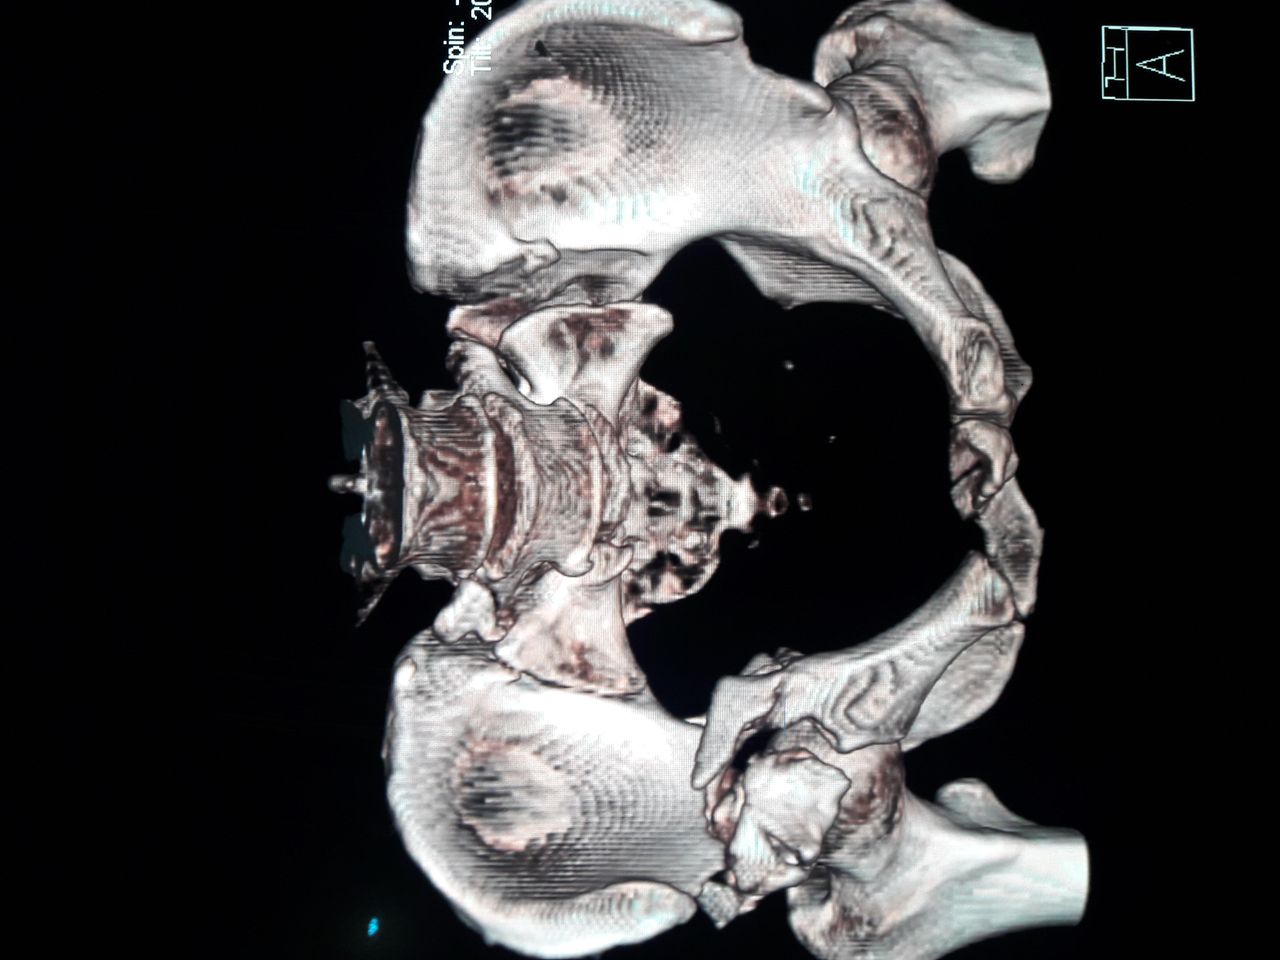

Alta Especialidad en cirugia de Cadera y Pelvis.

- Reemplazo articular de cadera

- Desgaste de cadera

- Fracturas de cadera

- Displasia del desarrollo de la cadera